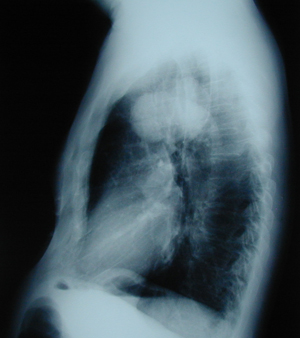

Εικόνα 2

Πλάγια ακτινογραφία θώρακος. Διακρίνεται μάζα στον άνω λοβό στο ύψος του αορτικού τόξου.